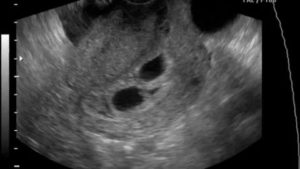

Может ли УЗИ не увидеть двойню?

Начиная с 7–8 акушерской недели некоторые сонологи выполняют абдоминальное ультразвуковое исследование. В это время видно беременность на УЗИ, но все зависит от качества аппаратуры и опыта диагноста. Но все же врачи настаивают на том, что на маленьком сроке лучше отдавать предпочтение трансвагинальному УЗИ для определения беременности.

Стандартно через живот смотрят беременную начиная с 10–12 недели. В это время не только видно плодное яйцо на УЗИ, но и хорошо виден эмбрион. В конце первого триместра можно уже качественно оценить генетические параметры зародыша. В это время, рассматривая эмбрион на УЗИ, диагност может определить таки отклонения в развитии: